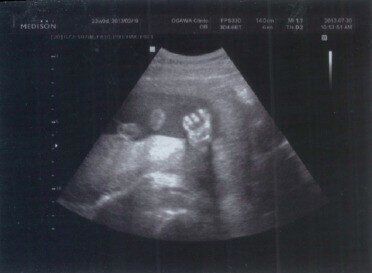

★妊娠23週:手

手が写っている写真。手は足に比べてとらえにくいといわれますが、指がくっきり。